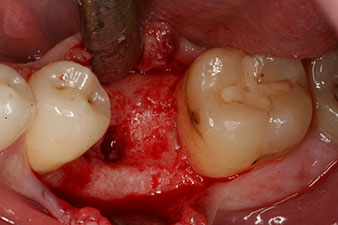

Имплантът е поставен както е планирано след цялостно отстраняване на гранулационната тъкан (blueSky, bredent).

Въртящият момент, използван за машинно-задвижвано поставяне, е 43 Ncm. Освен това, след завинтване на измервателния щифт (SmartPeg), специално пригоден за импланта, стойността на ISQ се измерва със сондата на W&H Osstell ISQ модула.

Този модул е допълнителна екстра към Implantmed на W&H и е закачен към имплантологичния мотор (виж фиг. 11). Липсата на ISQ стойност непосредствено след поставянето е 64 оровестибуларно и 68 мезиодистално (максимална стойност = 100).

Тези стойности могат да показват отворено лечение или дори имедиатно възстановяване. Поради недостатъчния обем на кресталната кост при импланта, областта е подсилена с костните частици, събрани по време на препарацията на имплантното ложе и зашити, за да се изолира слюнката.